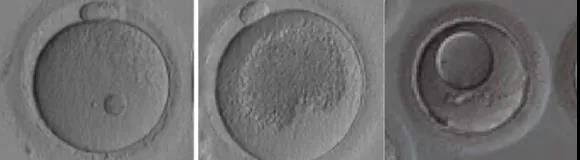

成熟的卵子大致為圓形,直徑約130um。主要有三個部分組成:

1、最外面的環狀結構是透明帶,為卵子提供安全的屏障,在受精過程中防止多條精子同時進入卵子而導致多精受精,并在早期發育過程中對維持胚胎的立體結構發揮重要的作用。

2、卵母細胞,也就是卵子的最核心部分,與精子結合形成受精卵進而發育為胚胎。

3、第一極體的出現則意味著卵子已經發育成熟,做好了迎接精子受精的準備。

正常形態的成熟卵子應該為圓形、胞漿均勻、顆粒均勻、卵周隙內無雜質、第一極體形態正常以及透明帶形態正常。在試管嬰兒助孕中,卵母細胞的評分與臨床妊娠結局有一定的相關性。

人的卵母細胞在胎兒出生時一直處于休眠狀態,青春期開始逐漸進入成熟發育的階段。此時的卵母細胞核較大,稱為生發泡,即GV期卵子。在排卵前的36-48小時,生發泡破裂,這個階段的卵子稱為MI卵子。LH峰值后36-40小時,卵子完成減數分裂,排除第一極體,發育成熟為MII卵子。